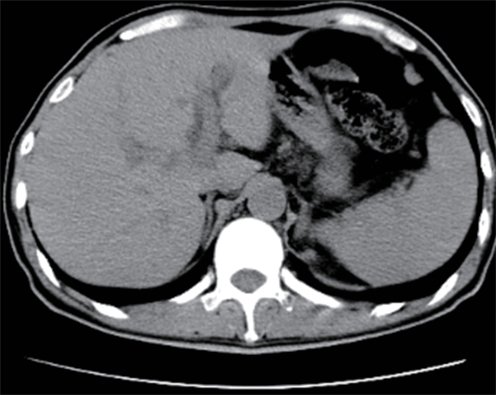

Value of internal stratification analysis of abdominal wall muscles in predicting complications after orthotopic liver transplantation

Xin SHI, Chongxiao LIANG, Bei ZHANG, Jiping WANG

2025, 41(2): 314-321. DOI: 10.12449/JCH250218

Abstract(759) HTML (355) PDF (3265KB)(57)

Abstract:

Objective  To divide the muscle into different subzones according to different density ranges using the stratified analysis on the basis of myosteatosis, and to investigate the effect of muscle density changes on complications (Clavien-Dindo grade ≥Ⅲ) after orthotopic liver transplantation (OLT).  Methods  A retrospective analysis was performed for the medical records of 145 patients who underwent OLT in The First Hospital of Jilin University from May 2013 to September 2020, and with the plain CT scan images of the largest level of lumbar 3 vertebrae of each patient as the original data, Neusoft Fatanalysis software was used to measure related muscle parameters. The independent-samples t test was used for comparison of normally distributed continuous data between two groups, and the Mann-Whitney U test was used for comparison of non-normally distributed continuous data between two groups. The chi-square test or Fisher test was for comparison of categorical data between two groups. RIAS software was used to extract clinical features and perform analysis and modeling, and three machine learning models of logistic regression (LR), support vector machine (SVM), and random forest (RFC) were constructed. The receiver operating characteristic (ROC) curve, the calibration curve, and the decision curve were plotted for each model to calculate the area under the ROC curve (AUC), sensitivity, specificity, precision, F1 score, and accuracy.  Results  The three machine learning models of LR-C, SVM-C, and RFC-C were established based on the 7 clinical features before muscle stratification analysis, among which the RFC-C model had an AUC of 0.803, a sensitivity of 0.588, and a specificity of 0.778 in the test set. Among the models of LR-CS, SVM-CS, and RFC-CS established based on the 16 clinical features after muscle stratification analysis, the LR-CS and SVM-CS models had an AUC of 0.852 in the test set, with a sensitivity of 0.765 and 0.706, respectively, and a specificity of 0.889 and 0.926, respectively. Comparison of the AUC, sensitivity, specificity, precision, F1 score, and accuracy of each model in the test set before and after muscle stratification analysis showed that there were improvements in the parameters of the predictive model after muscle stratification analysis. Comparison of the decision curves and calibration curves of each predictive model showed that the LR-CS and SVM-CS models had good efficacy in predicting postoperative complications (Clavien-Dindo grade≥Ⅲ) in OLT patients.  Conclusion  On the basis of myosteatosis, the division of the muscle into different subzones according to different densities using the stratified analysis has a certain value in predicting postoperative complications in patients with OLT.